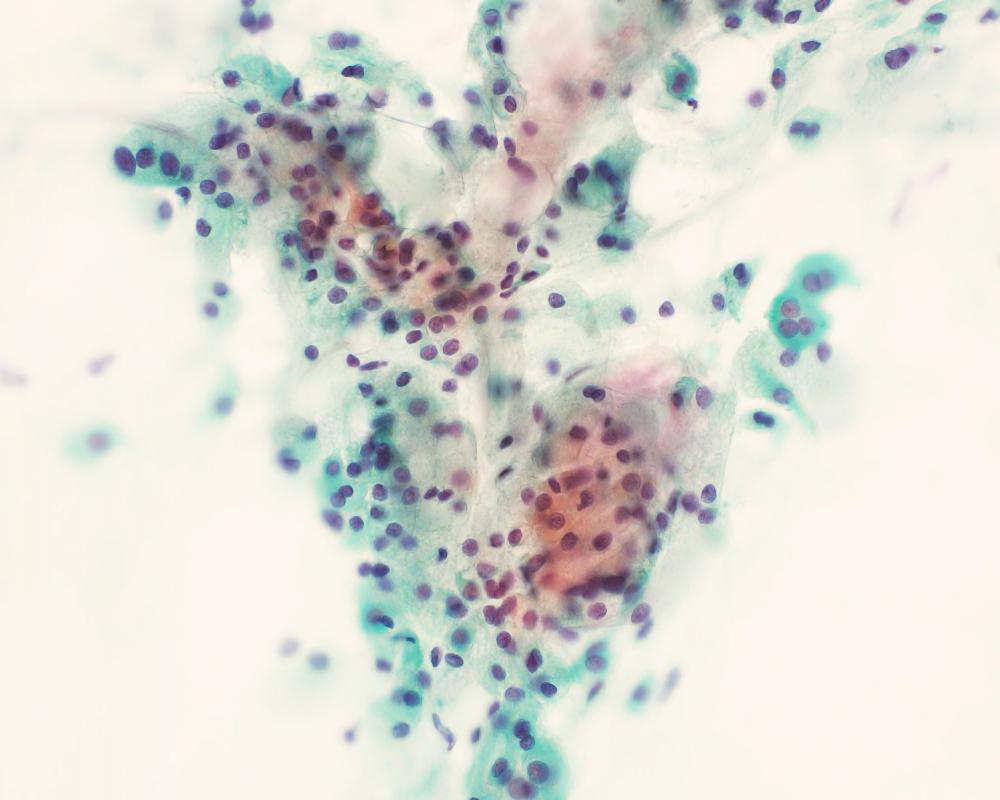

第38回日本臨床細胞学会九州連合会学会(熊本)スライドカンファレンス症例3

種別:消化器・口腔

出題:甲斐 敬太 佐賀大学医学部附属病院病理部

| 年齢 | 60代 | 性別 | 男性 |

| 採取部位 | 胆汁 | 採取方法 | 経皮経肝胆道ドレナージ |

既往歴:潰瘍性大腸炎治療中。

現病歴:難治性の十二指腸潰瘍を合併し、通過障害をきたしていた。閉塞性黄疸が出現し、精査で原発性硬化性

胆管炎が疑われた。減黄目的に経皮経肝胆道ドレナージが行われ、胆汁が提出された。なお、狭窄部の

胆管と十二指腸潰瘍部から生検が行われたが、悪性所見は指摘できなかった。

| 正解 | 5.腺癌 |

▼選択肢及び投票結果

| 1.急性胆管炎 (反応性異型) | 1件 | (1.0%) | |

| 2.原発性硬化性胆管炎 (反応性異型) | 25件 | (24.0%) | |

| 3.Low-grade BilIN | 31件 | (29.8%) | |

| 4.Low-grade IPNB | 19件 | (18.3%) | |

| 5.腺癌 | 28件 | (26.9%) | |

| 投票総数 | 104件 | (100%) |